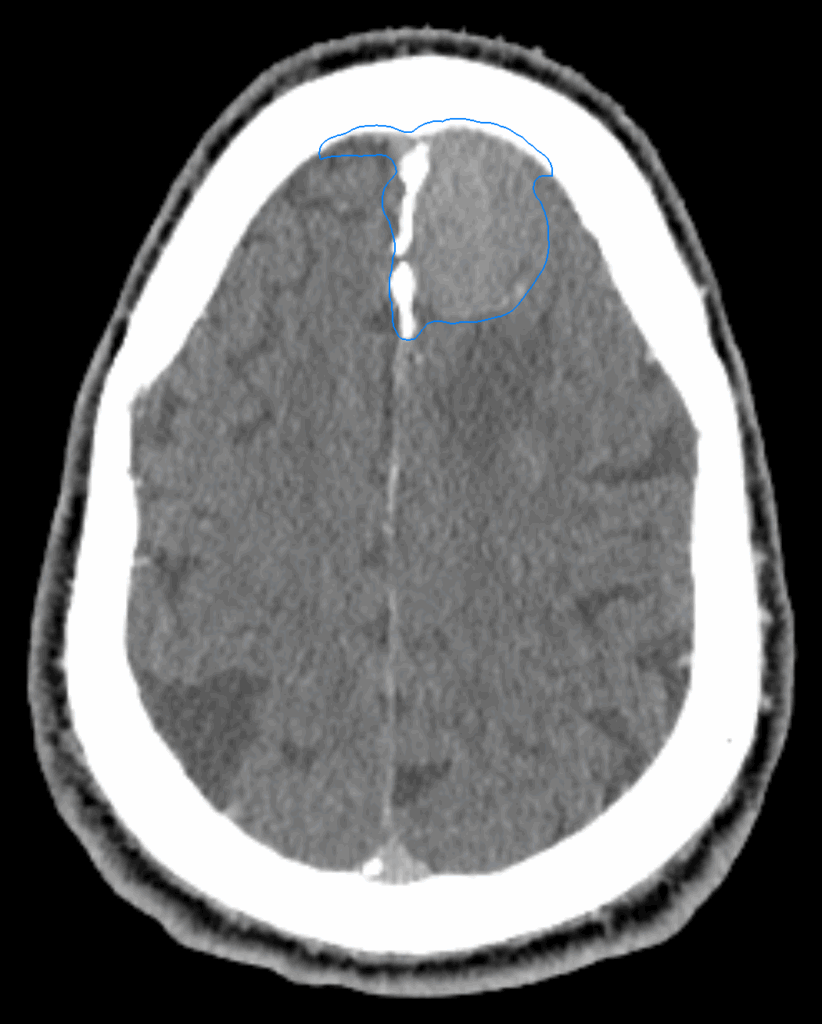

Planning CT Images